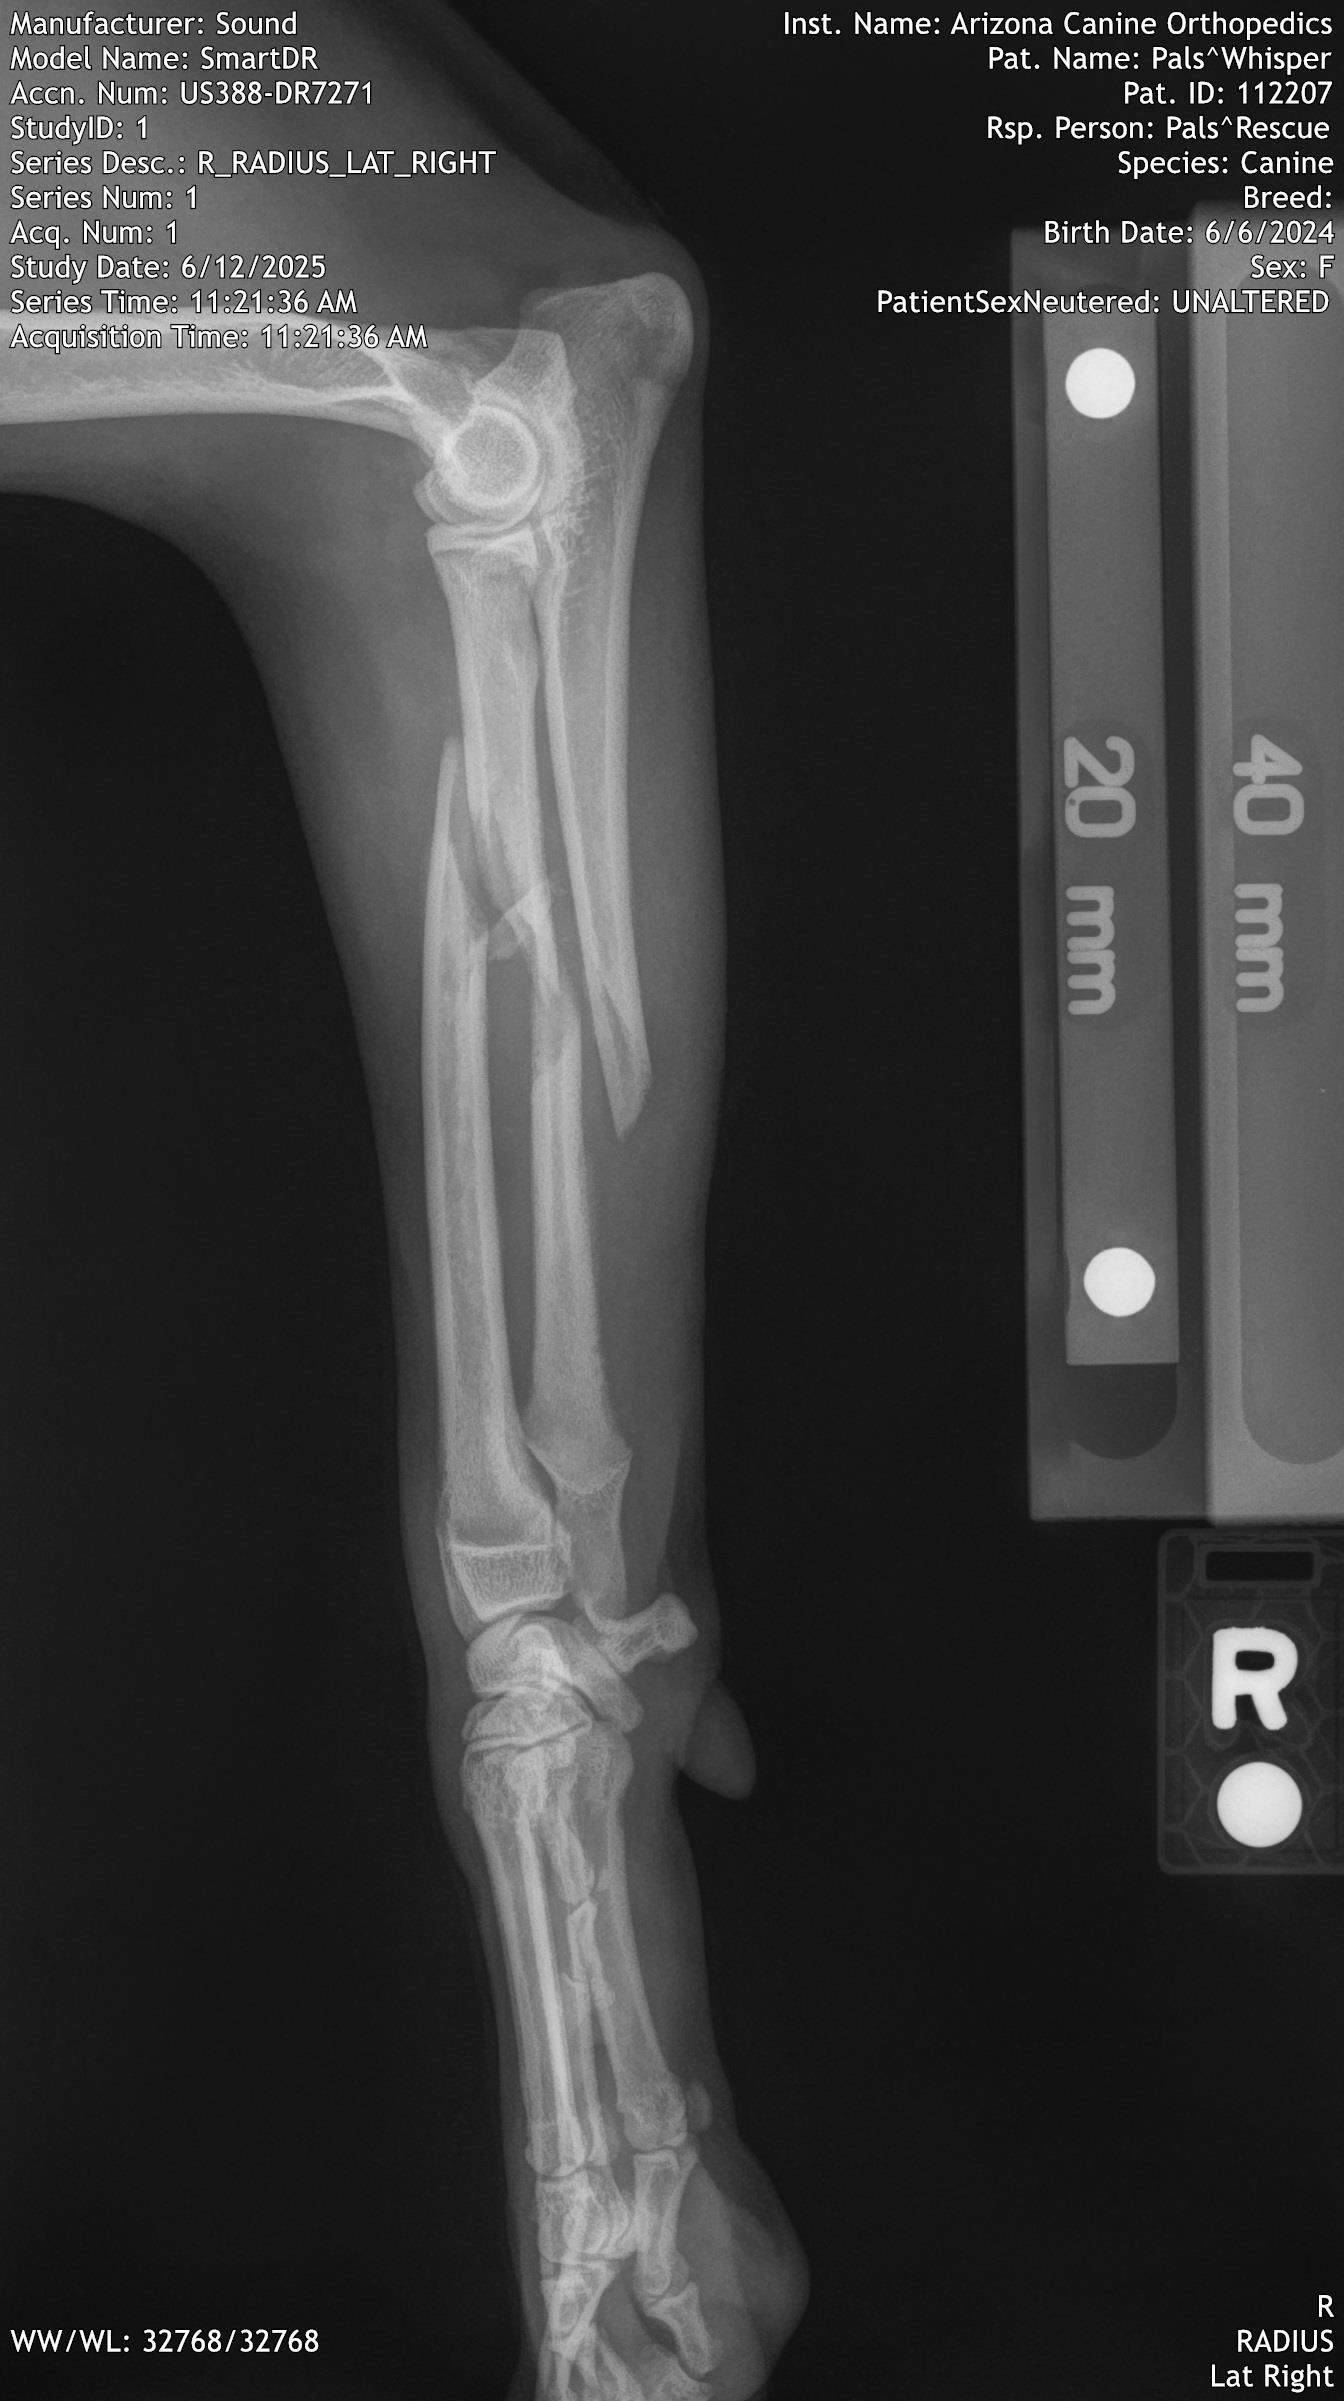

We immediately noticed there was something wrong with one of her front legs and were able to bring her to Friendship Pet Hospital. Dr. Lynne Hoban confirmed what we already suspected, the leg was broken

Because Whisper is under a year old and in good health, we decided to try and see if her leg could be saved. Dr. Hoban contacted Dr. Lirtzman of ACOSM and he agreed to try and save Whisper's leg.